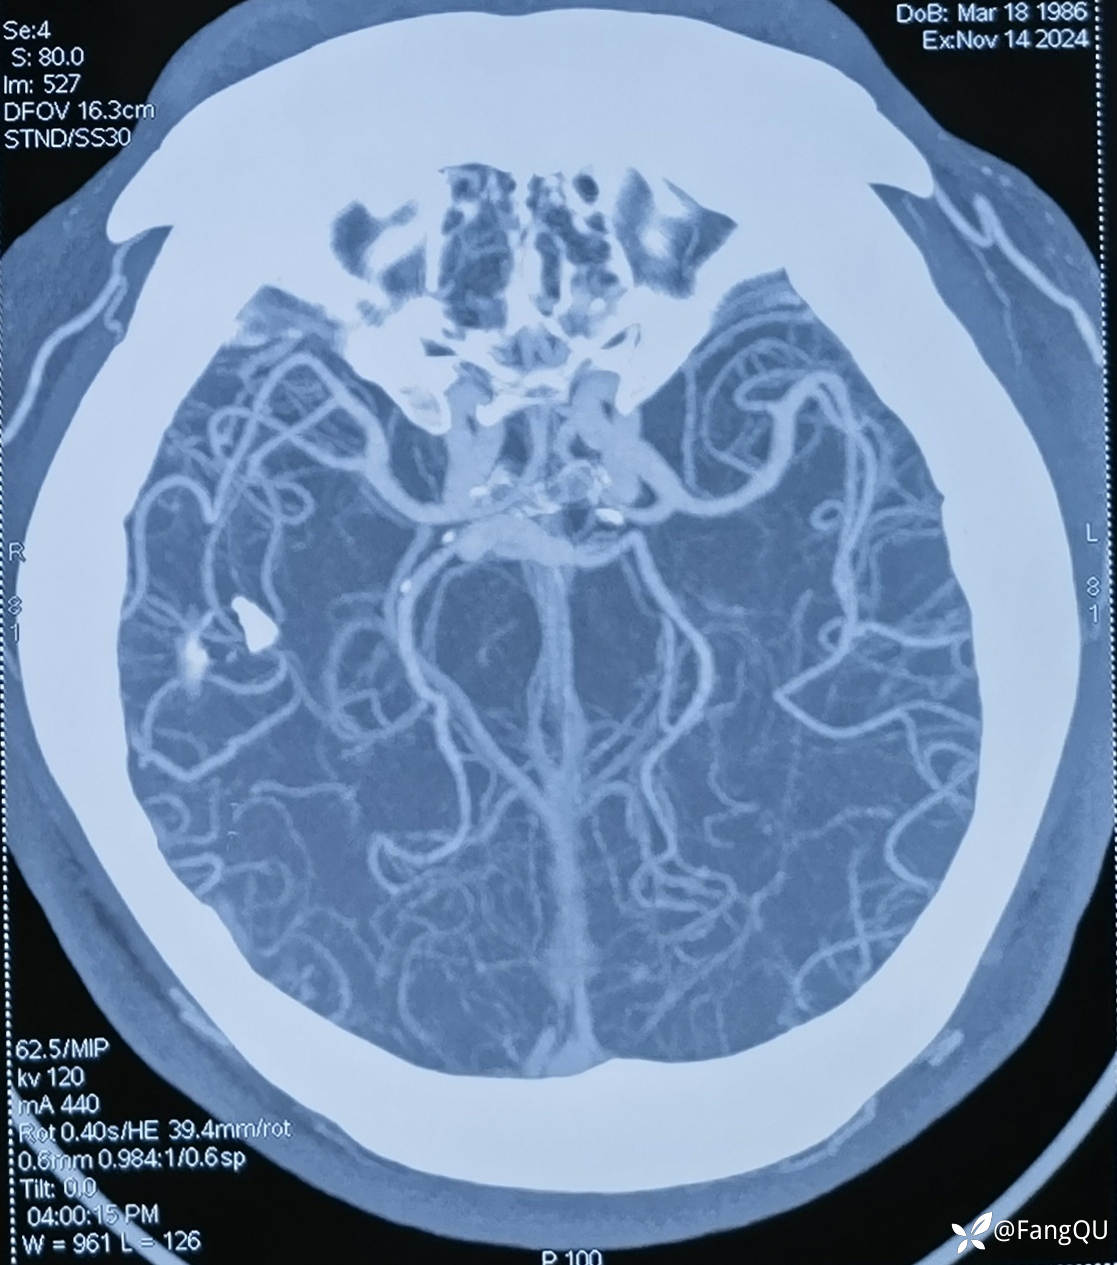

建议头颈CTA:见下

双侧椎动脉和基底动脉如此粗壮,咋还得脑梗死呢?

椎基底动脉扩张延长 (6)